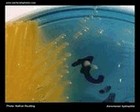

Staphylococcus aureus | - Beta-hemolysis on media with blood (sheep, horse)

| Beta-hemolysis on media with blood |

Beta hemolysis Staphylococcus aureus |

Staphylococcus aureus Beta hemolysis on blood agar |